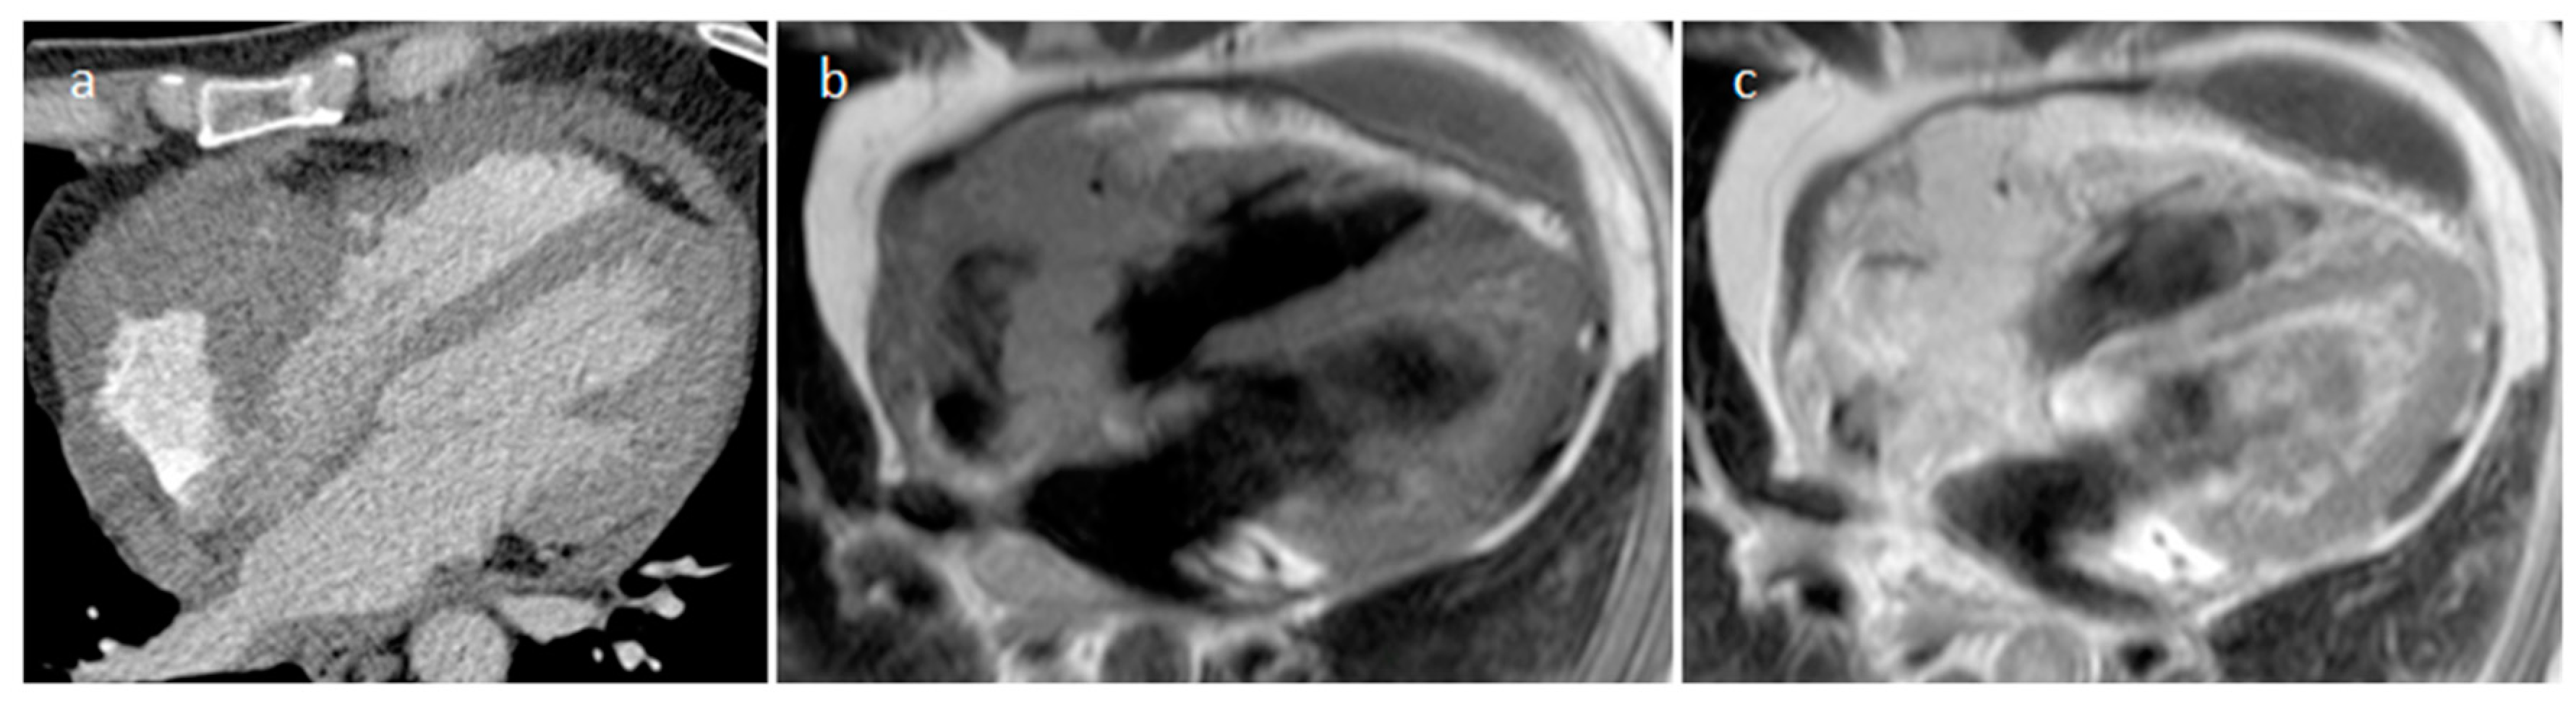

3.1. Thrombus

| Thrombus | Adulthood | LA, LAA (AF) LV (MI) | Asymptomatic, embolic events | Non-enhancing Intracardiac lesion | Acute: Low echodensity, rounded with smooth contours Chronic: High echodensity, linear or crescentic lesions along the endocardial surface | Low attenuation, no contrast enhancement, chronic thrombus may be calcified Usefulness of delayed CT imaging, as in the LAA stasis of blood can simulate a thrombus on early arterial images | Acute: hyper T1w and T2w Subacute: hyper T1w and hypo T2w Chronic: low T1w and T2w No enhancement. |